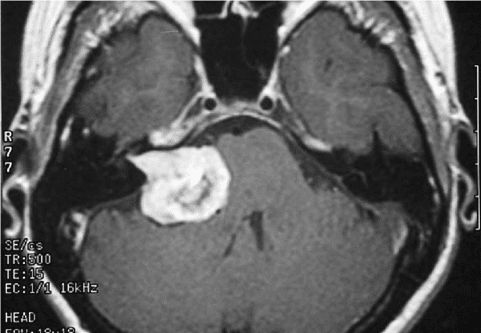

Є багато різних типів новоутворень НС. Деякі утворення є доброякісними, а деякі злоякісними. Також розрізняють:

- первинні, які виростають з клітин самої нервової системи,

- і вторинні, або метастатичні пухлини, які заносяться в головний, спинний мозок з потоком крові при пухлинах інших органів. Вторинні пухлини, як правило є злоякісними.

Гліоми – ці пухлини ростуть з клітин нейроглії головного або спинного мозку і включають астроцитоми, епендимоми, гліобластоми, олігоастроцітоми і олігодендрогліоми.

Медулобластоми – це найпоширеніші злоякісні пухлини головного мозку у дітей. Медулобластома виростає з клітин стовбуру мозку і має тенденцію поширюватися через спинномозкову рідину. Ці пухлини зустрічаються набагато рідше і у дорослих.

Вторинні

Вторинні (тобто метастатичні) пухлини ГМ це утворення, які результатом онкології, яка розпочалася в іншому місці вашого тіла, а потім поширилась (метастазувала) у ваш мозок.